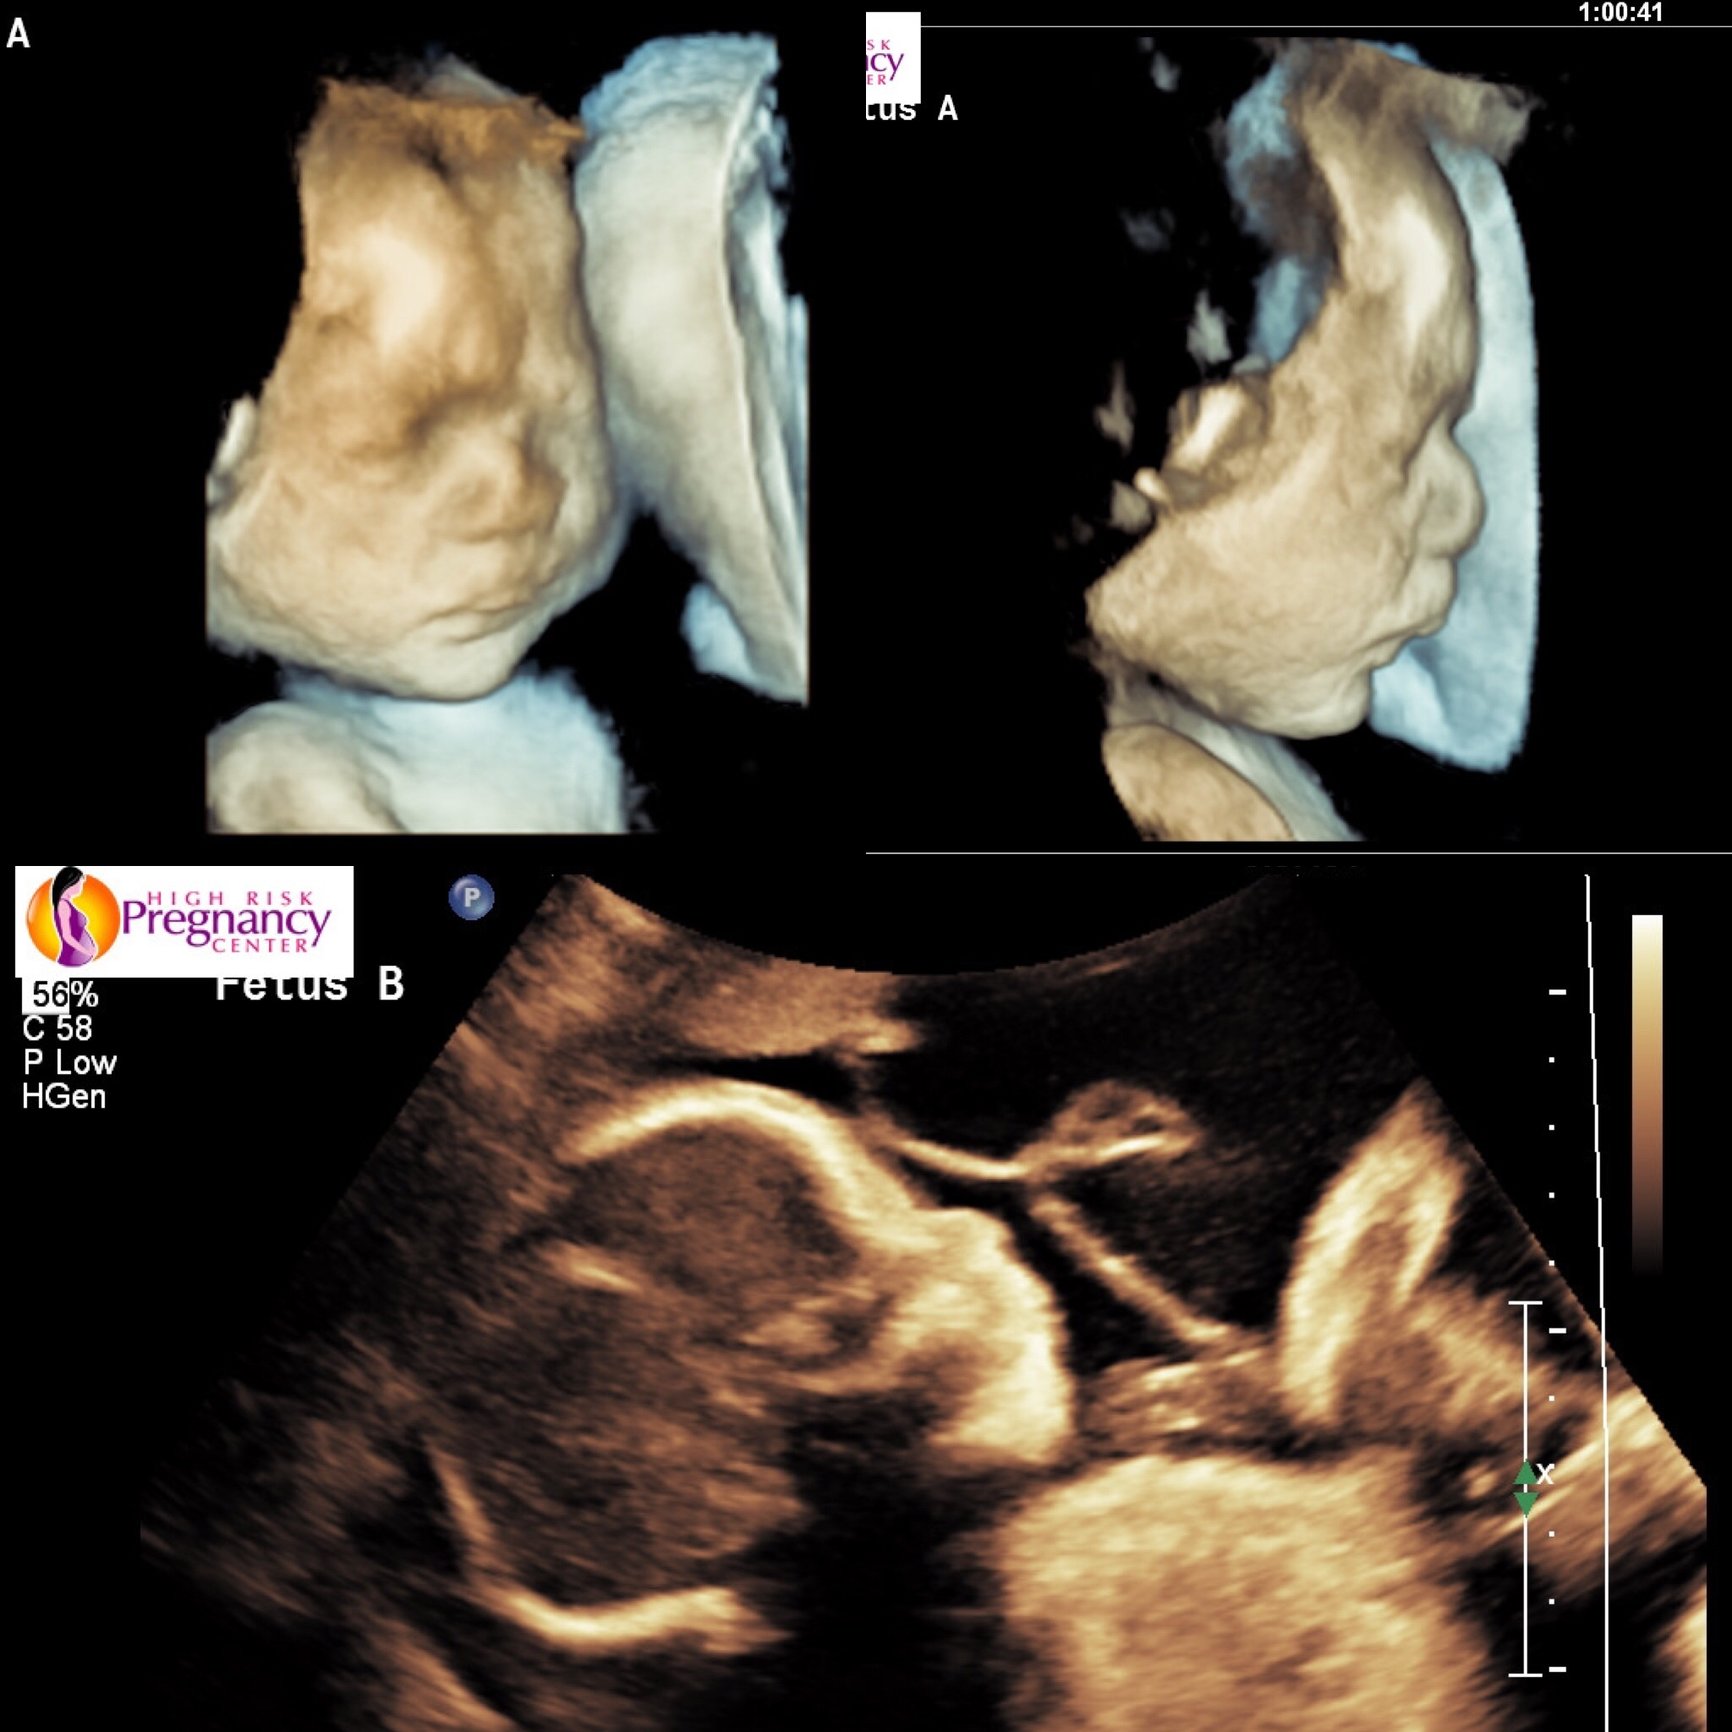

• How far along are you? 27w4d

How did your appointment go overall? Not great, pretty concerning and confusing

Any ultrasound or doppler? Ultrasound (fetal echocardiogram)

Did your doctor or midwife answer any questions or concerns you had? I didn't have questions or concerns before it really since I was just going back for them to get the pics they couldn't get last time, so this kind of just left me with a lot. I have to go back for a third try in a month because they still didn't get a clear pic of the one heart structure bc her head was tucked to her chest. The dr said from what they could see, it might be nothing or it might be something that would require surgery after birth. If they can't get it next time (if she's not magically stretched out flat instead of curled up at 32 weeks??), we'll have to wait until they can check after she's born to rule it out.